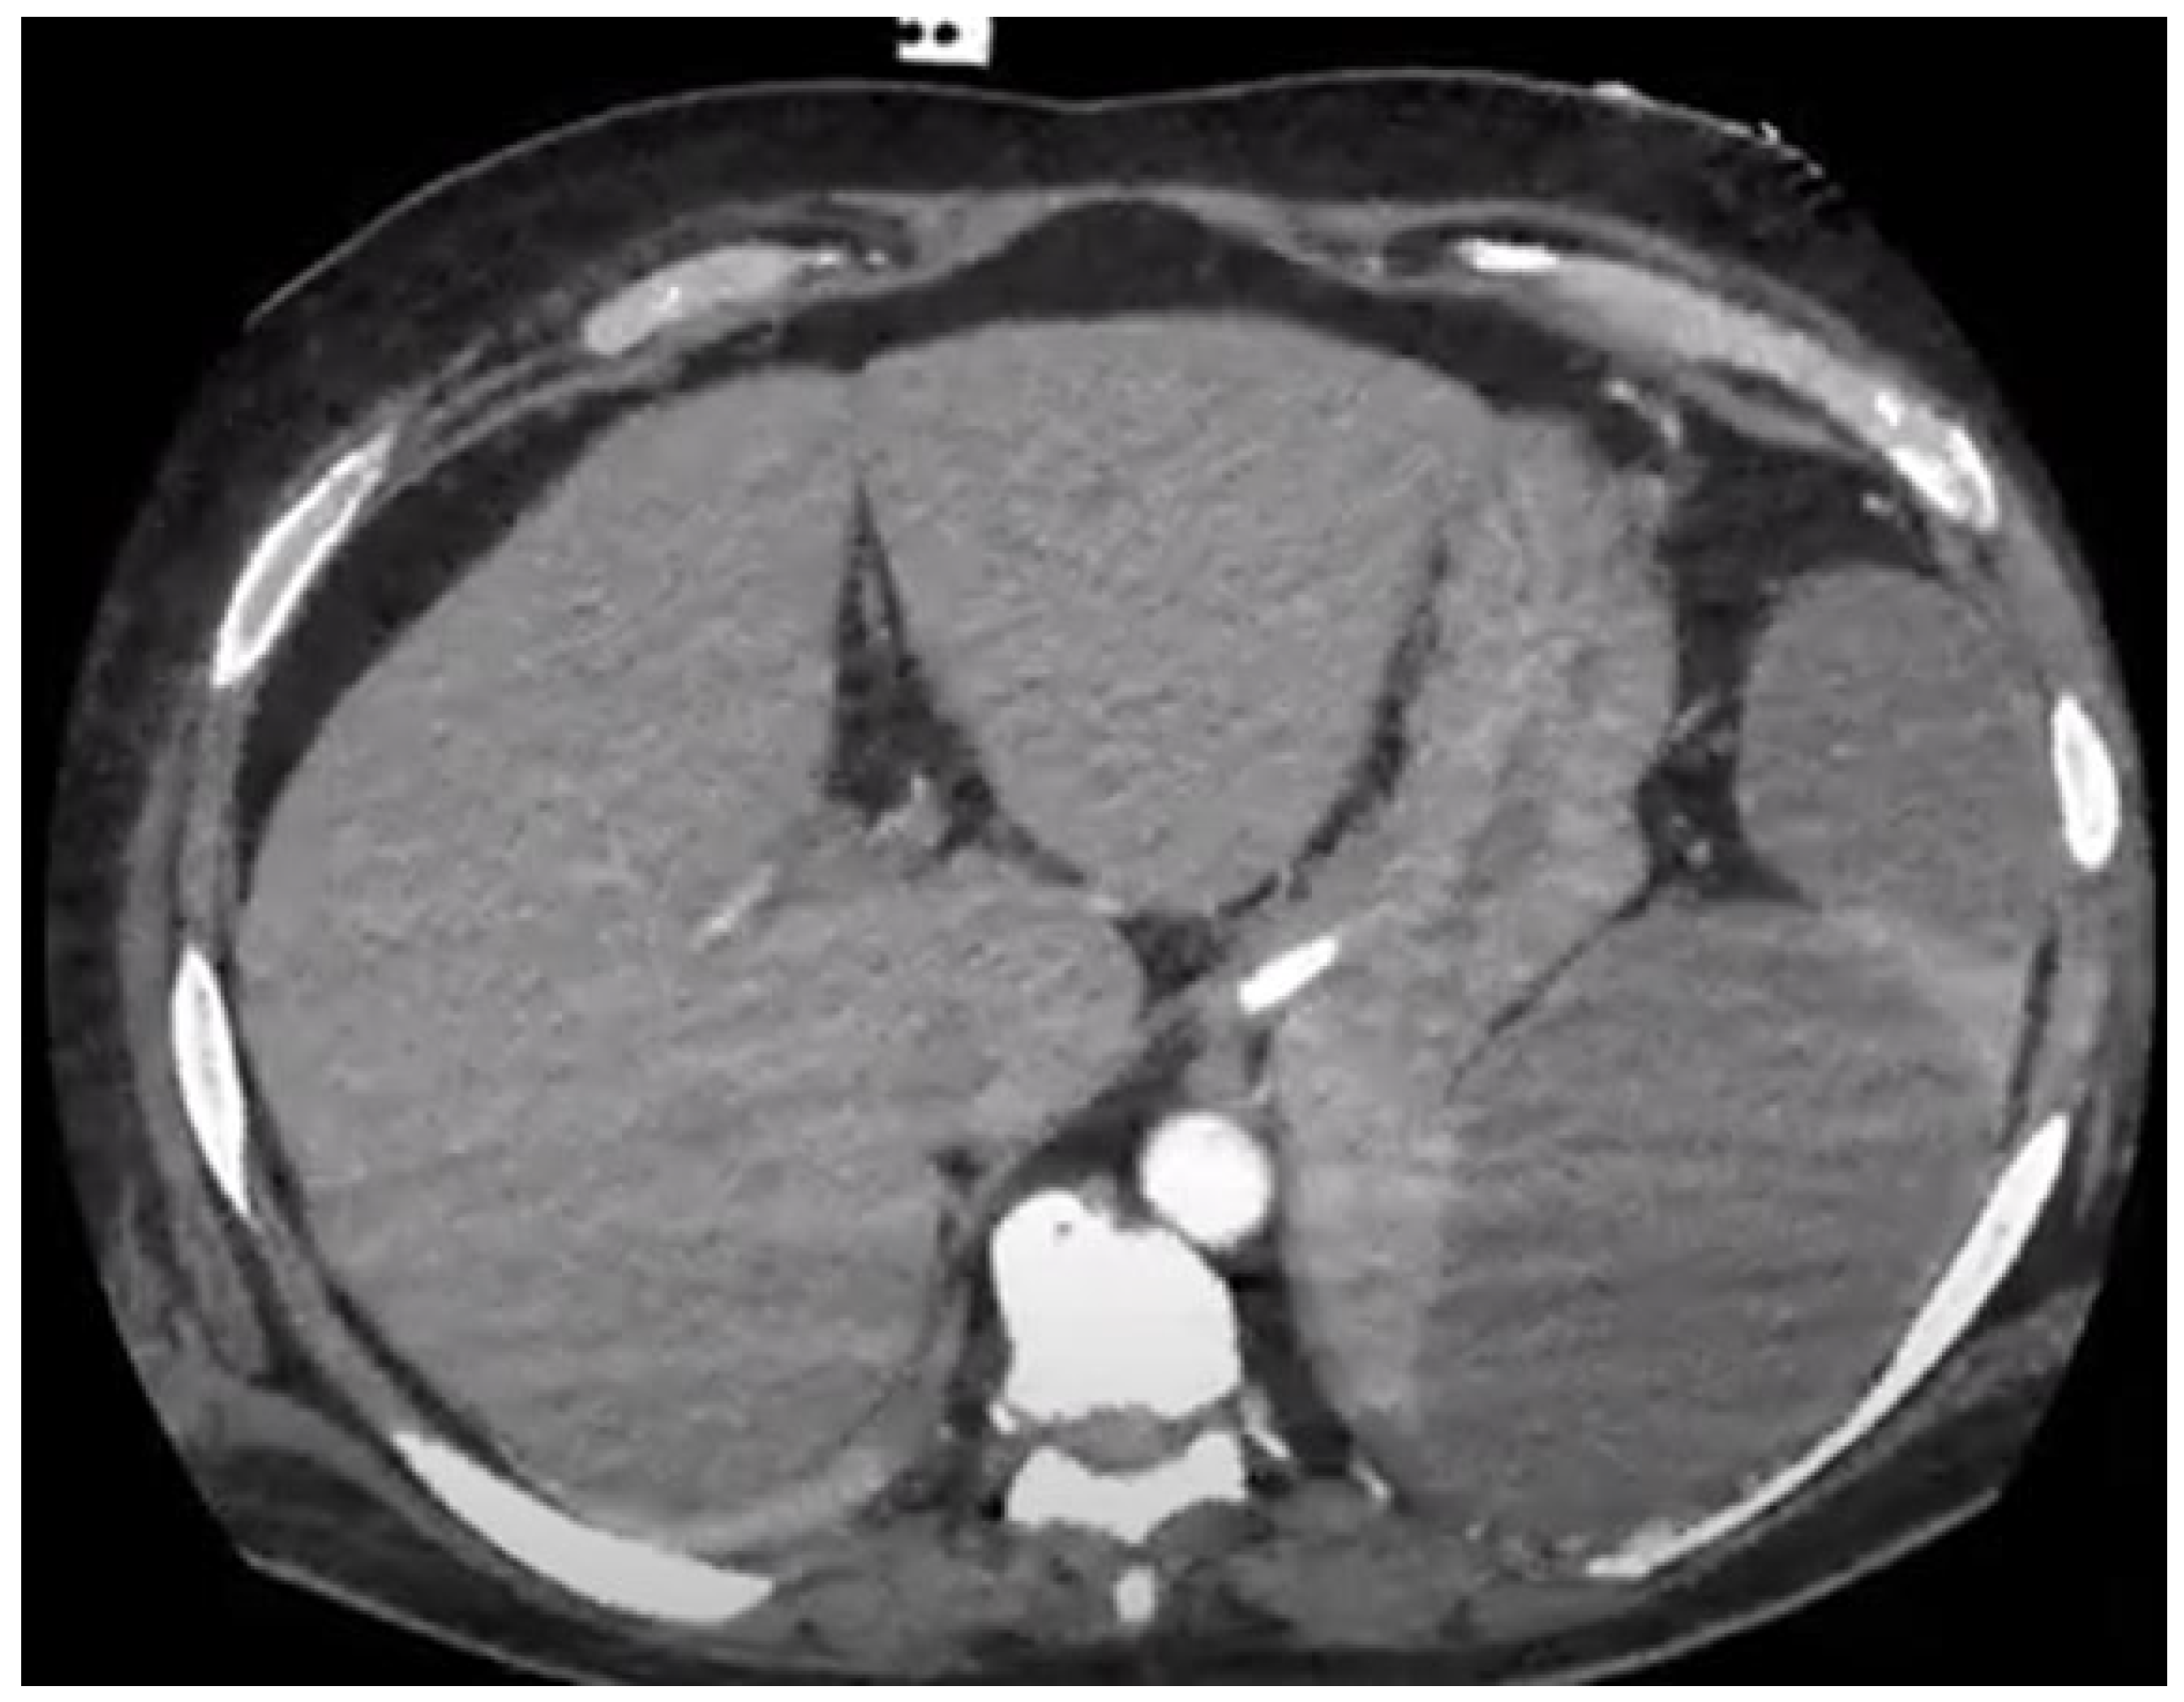

Splenic Embolism in Infective Endocarditis: A Systematic Review of the Literature with an Emphasis on Radiological and Histopathological Diagnoses

3. Results